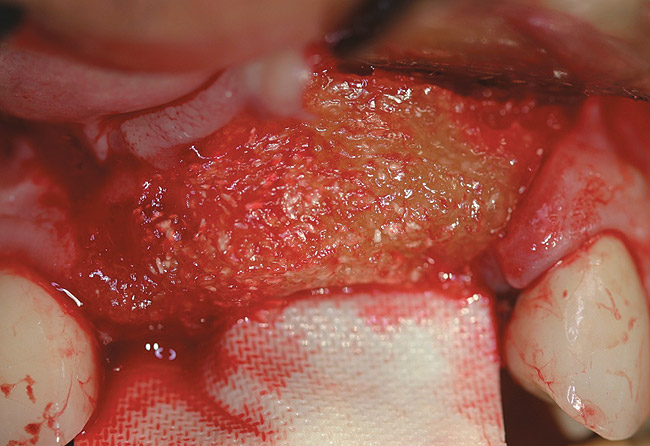

Figure 3  RegenerOss Allograft Putty molded to form the contours desired for the reconstructed ridge.

Figure 3